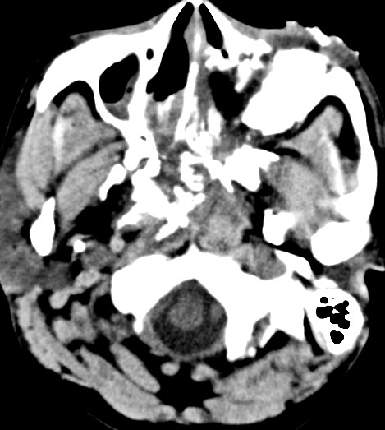

2014-9-29 CT